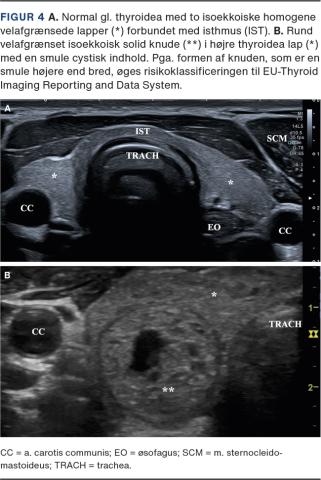

THYROIDEA

Gl. thyroidea ses kaudalt for cartilago thyroidea med to elongerede lapper forbundet med en tynd isthmus over midten af trachea (Figur 4). Gl. thyroidea-parenkymet ses på UL-skanning fint homogent og hyperekkoisk sammenlignet med den omkringliggende muskulatur. Gll. parathyroideae findes oftest ved øvre og nedre thyroideapol og kan normalt ikke visualiseres med UL-skanning.

Benigne adenomer er meget hyppige i gl. thyroidea, hvorfor UL-skanning heraf anvendes rutinemæssigt som screening [21]. EU-TIRADS-klassifikationssystem indeholder guidelines til selektering af de adenomer, hvor man har behov for yderligere udredning med finålsbiopsi pga. malignitetssuspicio [22]. Overordnet er rene cyster altid benigne, mens et solidt hypoekkoisk adenom i gl. thyroidea er mere malignitetsuspekt end et hyperekkoisk adenom [23]. Desuden øger UL-skanningskarakteristika såsom diffus afgrænsning, mikrokalcificeringer samt højere end bred-konfiguration risikoen for malignitet. Ved Graves’ sygdom og tyroiditis kan der ses diffust forstørret gl. thyroidea samt øget parenkymal Doppleraktivitet [24]. Gll. parathyroidea-adenomer kan oftest visualiseres ved UL-skanning modsat normale kirtler og er kendetegnede ved hypervaskularisering sammenlignet med omkringliggende thyroideavæv.